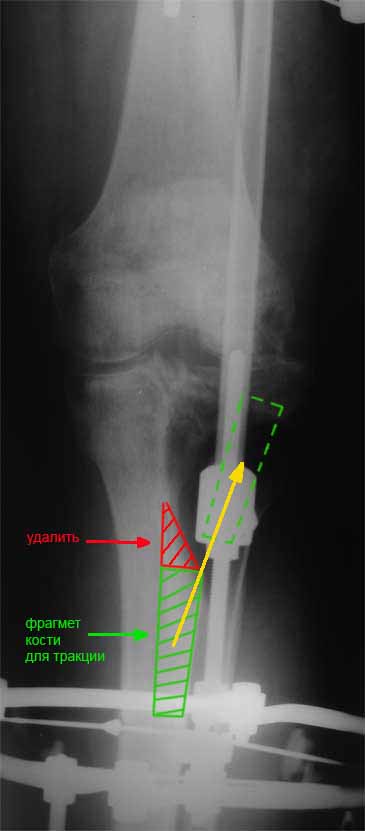

Я бы сделал пластику мягких тканей (торакодорзальный лоскут совместно с микрохирургами или пластику латеральной головкой икроножной мышцы) и выполнил бы краевой отщеп большеберцовой кости для его дистракции аппаратом в проксимальном направлении (рис. 1 – пример применения отщепа (авторство не мое), рис. 2 – схема предлагаемого варианта замещения дефекта кости).